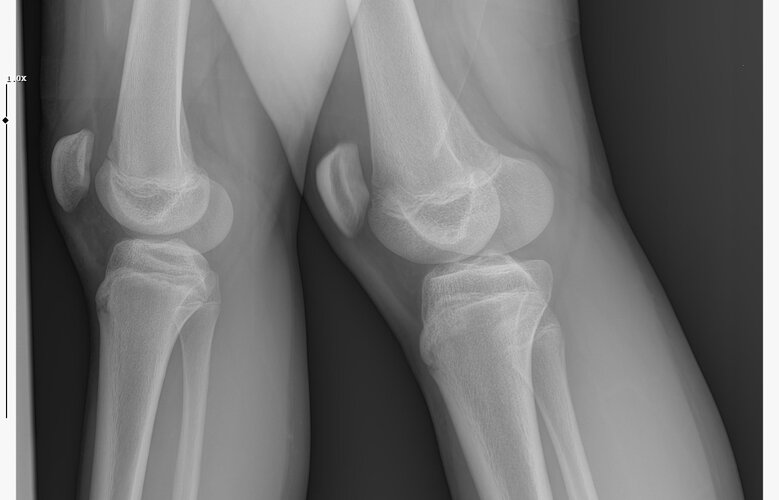

doktor bi sik bilmiyodur büyük ihtimalle plakları buraya at biz bakak

IMG 5959

röntgeni atar mısın?

• WhatsApp Image 2026-01-07 at 00.31.08 (4).jpeg

WhatsApp Image 2026-01-07 at 00.31.08 (4).jpeg

161.8 KB · Views: 0

kapanmaya baslamıs ama cok yakın degil

kemik yaşın 15 gibi 15'e çok yakın

anne baba boyun ve yaşını bilmiyorum sadece bu bilgilerle 171-175 arası diye tahmin ediyorum röntgen ile.

normalde anne babana göre 171-176 olman gerek zaten. kemik yaşın ve şuanki boyun ile yapılacak tahmin anne baban ile yapılabilecek tahminle nerdeyse birebir aynı yani büyük ihtimal o civarlar olursun bence